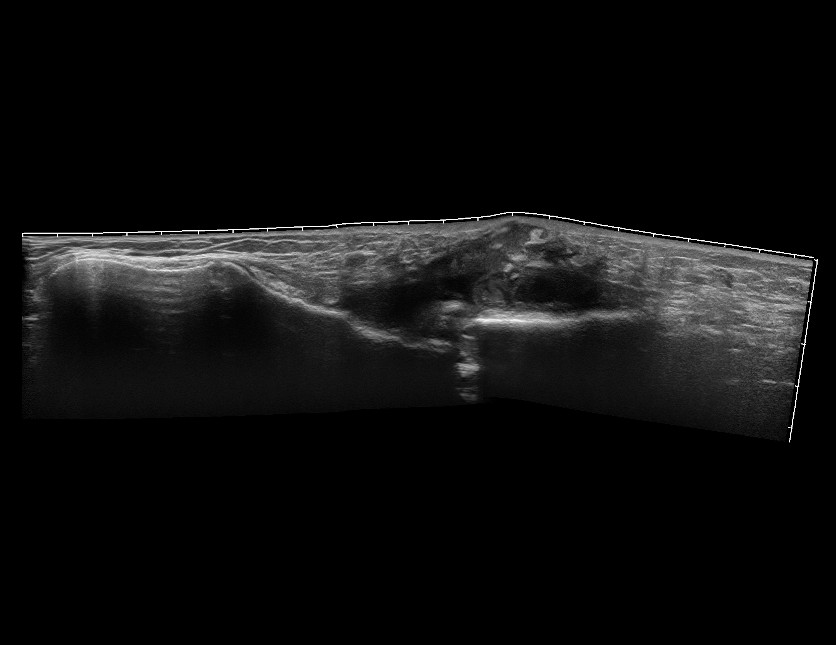

Мужчина, перелом грудины.

Пункция под контролем УЗИ